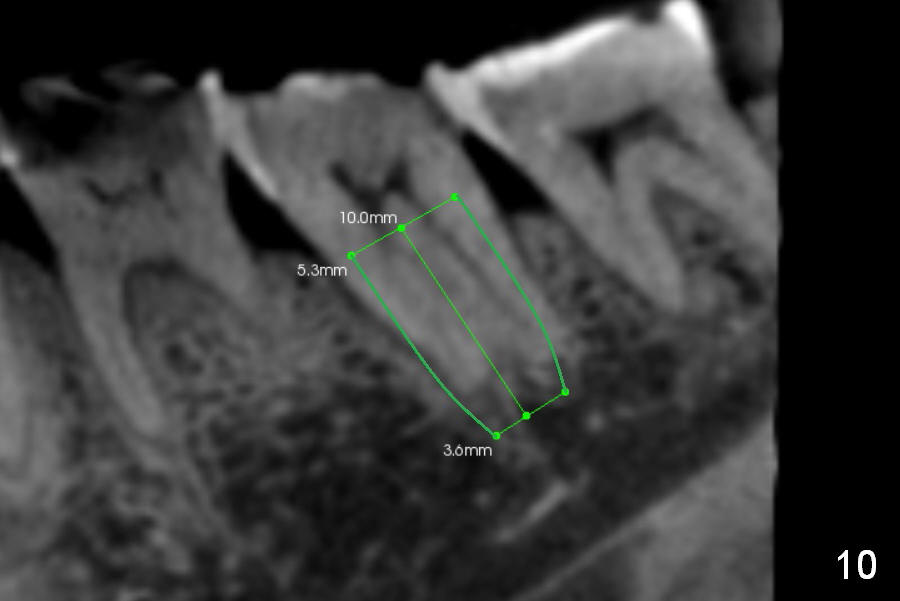

CBCT Analysis of the lower left 2nd molar reveals that the proper implant size is 5.3x10 mm (Fig.8-10). The root is C shaped; limiting factor is buccolingual width (5.5 mm, Fig.8 (axial section)). The major difference between #18 and 31 is the resorption of the buccal plate of the latter (traumatic extraction, Fig.9 (F: submandibular fossa)).